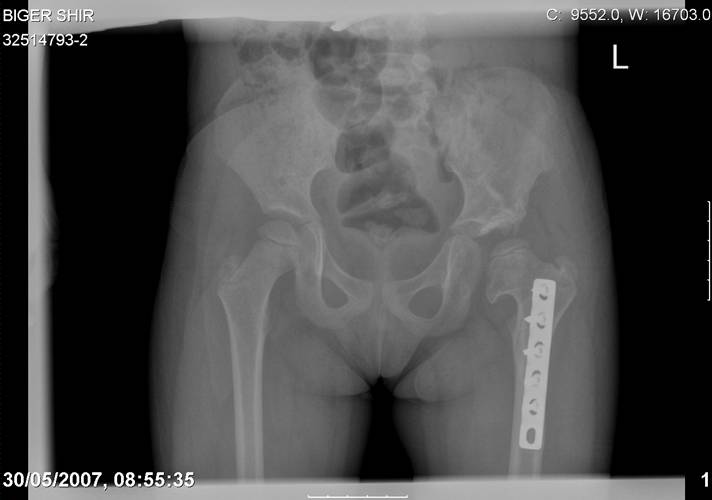

Здравствуйте, уважаемые коллеги.Обратилась девочка 6-ти лет из жалобами на боль в левом т/б суставе,хромоту Из анамнеза : ребенок лечился с рождения по поводу врожденного вывиха бедер. В возрасте 3- х лет в одной из клиник была выполнена остеотомия таза по Пембертону и варизирующая остеотомия бедра слева, справа - остеотомия таза по Солтеру и остеотомия бедра. Посоветуйте тактику лечения. С уважением Ihor

Smotritsya parshivo konechno(pseudoacetabulum,partial AVN), no v6 let ya by popytalsya ispravit chto moghno:shortening (ne boyatsya ubrat bolshoi fragment),derotation(30 gradusov ne bolshe)+pelvic osteotomy in true acetabuluam area.Obyazatelno takghe open reduction with wide capsular exposure.

Navernoe Dega

Chto by ne byt goloslovnym posilau vam svoi sluchai gde sdelal vse chto napisal vyshe

Уважаемой Ihor! Следует дообследовать ребенка, проведя РКТ или МРТ. Необходимо установить взаимоотношение головки бедренной кости и вертлужной впадины слева, оценить угол антеторсии и истинный ШДУ. Далее решать вопрос об оперативном лечении. Скорее всего показана деторсионно-варизирующая остеотомия в межвертельной области левого бедра и остеотомия таза типа Солтера (хотя ацетабулярный индекс великоват, т.е. более 30-35 градусов). Справа следует понаблюдать и периодически проводить курсы ФТО и ЛФК. Если Вы не имеете опыта реконструктивной хирургии ТБС у детей, то лучше отправить пациента к детским ортопедам. АИФ